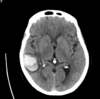

14

Q

35 anos, Masculino

A

Craniofaringioma adamantinomatoso

26

Criança

Craniofaringioma adamantinomatoso Crianças Lesão suprasselar com componente sólido e cístico; lobulado; calcificação anelar ou nodular presente em quase TODOS os craniofaringeomas pediátricos; Componente cístico proeminente e componente sólido pequeno, mas com realce.

60 anos

Craniofaringioma Papilar Realce periférico e heterogêneo Calcificação não é comum Adultos

Craniofaringioma papilar Comum em adultos Calcificação é rara Componente cístico pode ocorrer mas não é um achado proeminente

200